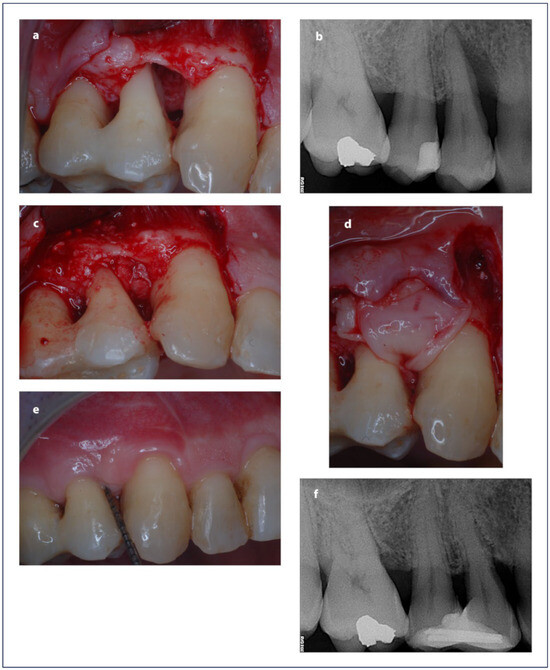

2.9. Surgical Procedure